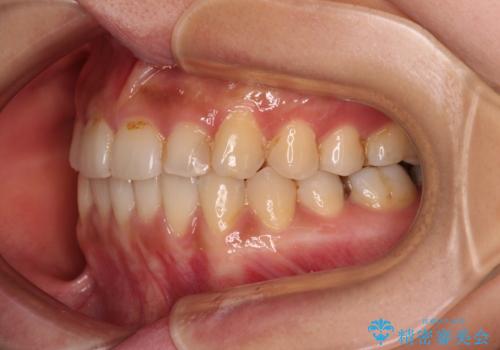

前歯のデコボコとクロスバイト インビザラインによる矯正治療

- 上下のクロスバイトと前歯のデコボコを気にして来院された患者様です。

骨格的に下顎がやや前方にあり、奥歯にクラウンが装着されているため、矯正治療後半の不安定な咬み合わせを避けるのであればワイヤー矯正がおすすめとなりますが、希望によりインビザラインにて治療を行うこととしました。

インビザラインを用い、IPR(歯と歯の間を削る)と歯列全体を拡大させることで、歯並びを整えていくこととしました。

懸念されたとおり、右下のクラウン部分が全く咬み合わず、仕上げの段階で治療期間が長くなりました。